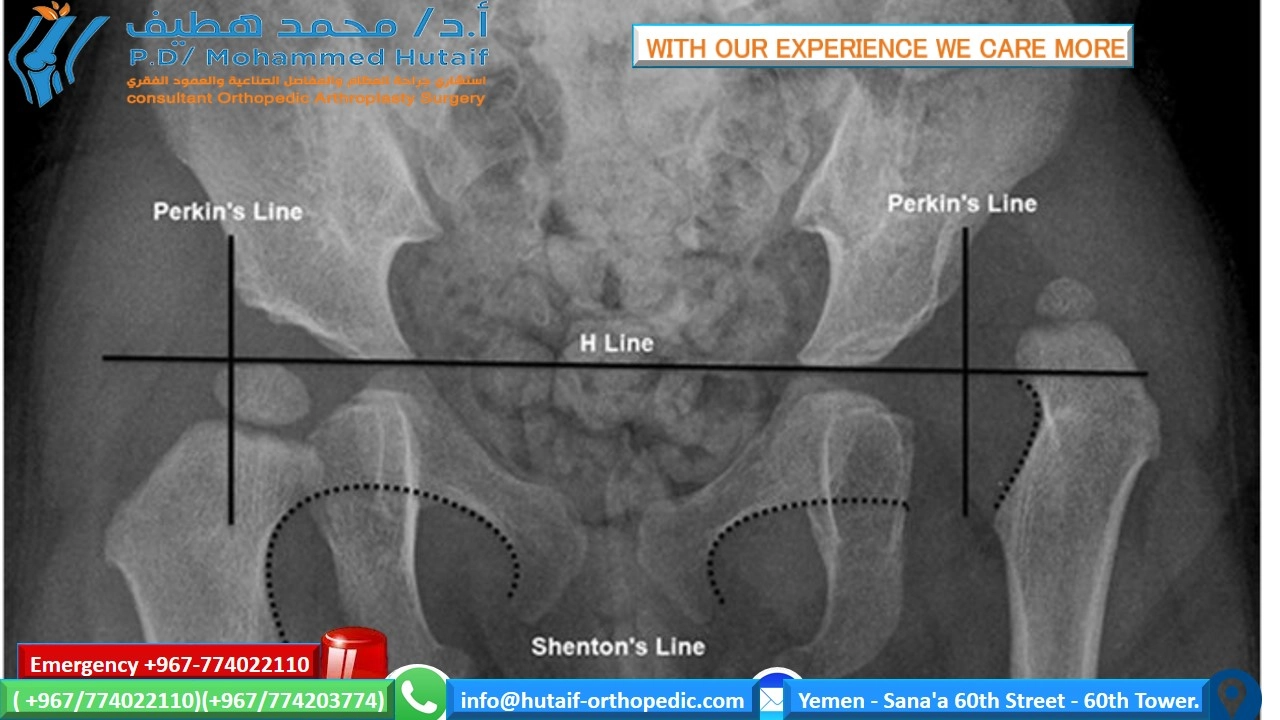

Radiographic Analysis

Standard weight-bearing anteroposterior (AP), lateral, and sesamoid axial radiographs are mandatory.

1. Hallux Valgus Angle (HVA): The angle between the longitudinal axes of the first metatarsal and the proximal phalanx.

2. Intermetatarsal Angle (IMA): The angle between the longitudinal axes of the first and second metatarsals.

3. Distal Metatarsal Articular Angle (DMAA): The relationship of the articular surface of the metatarsal head to the longitudinal axis of the metatarsal.